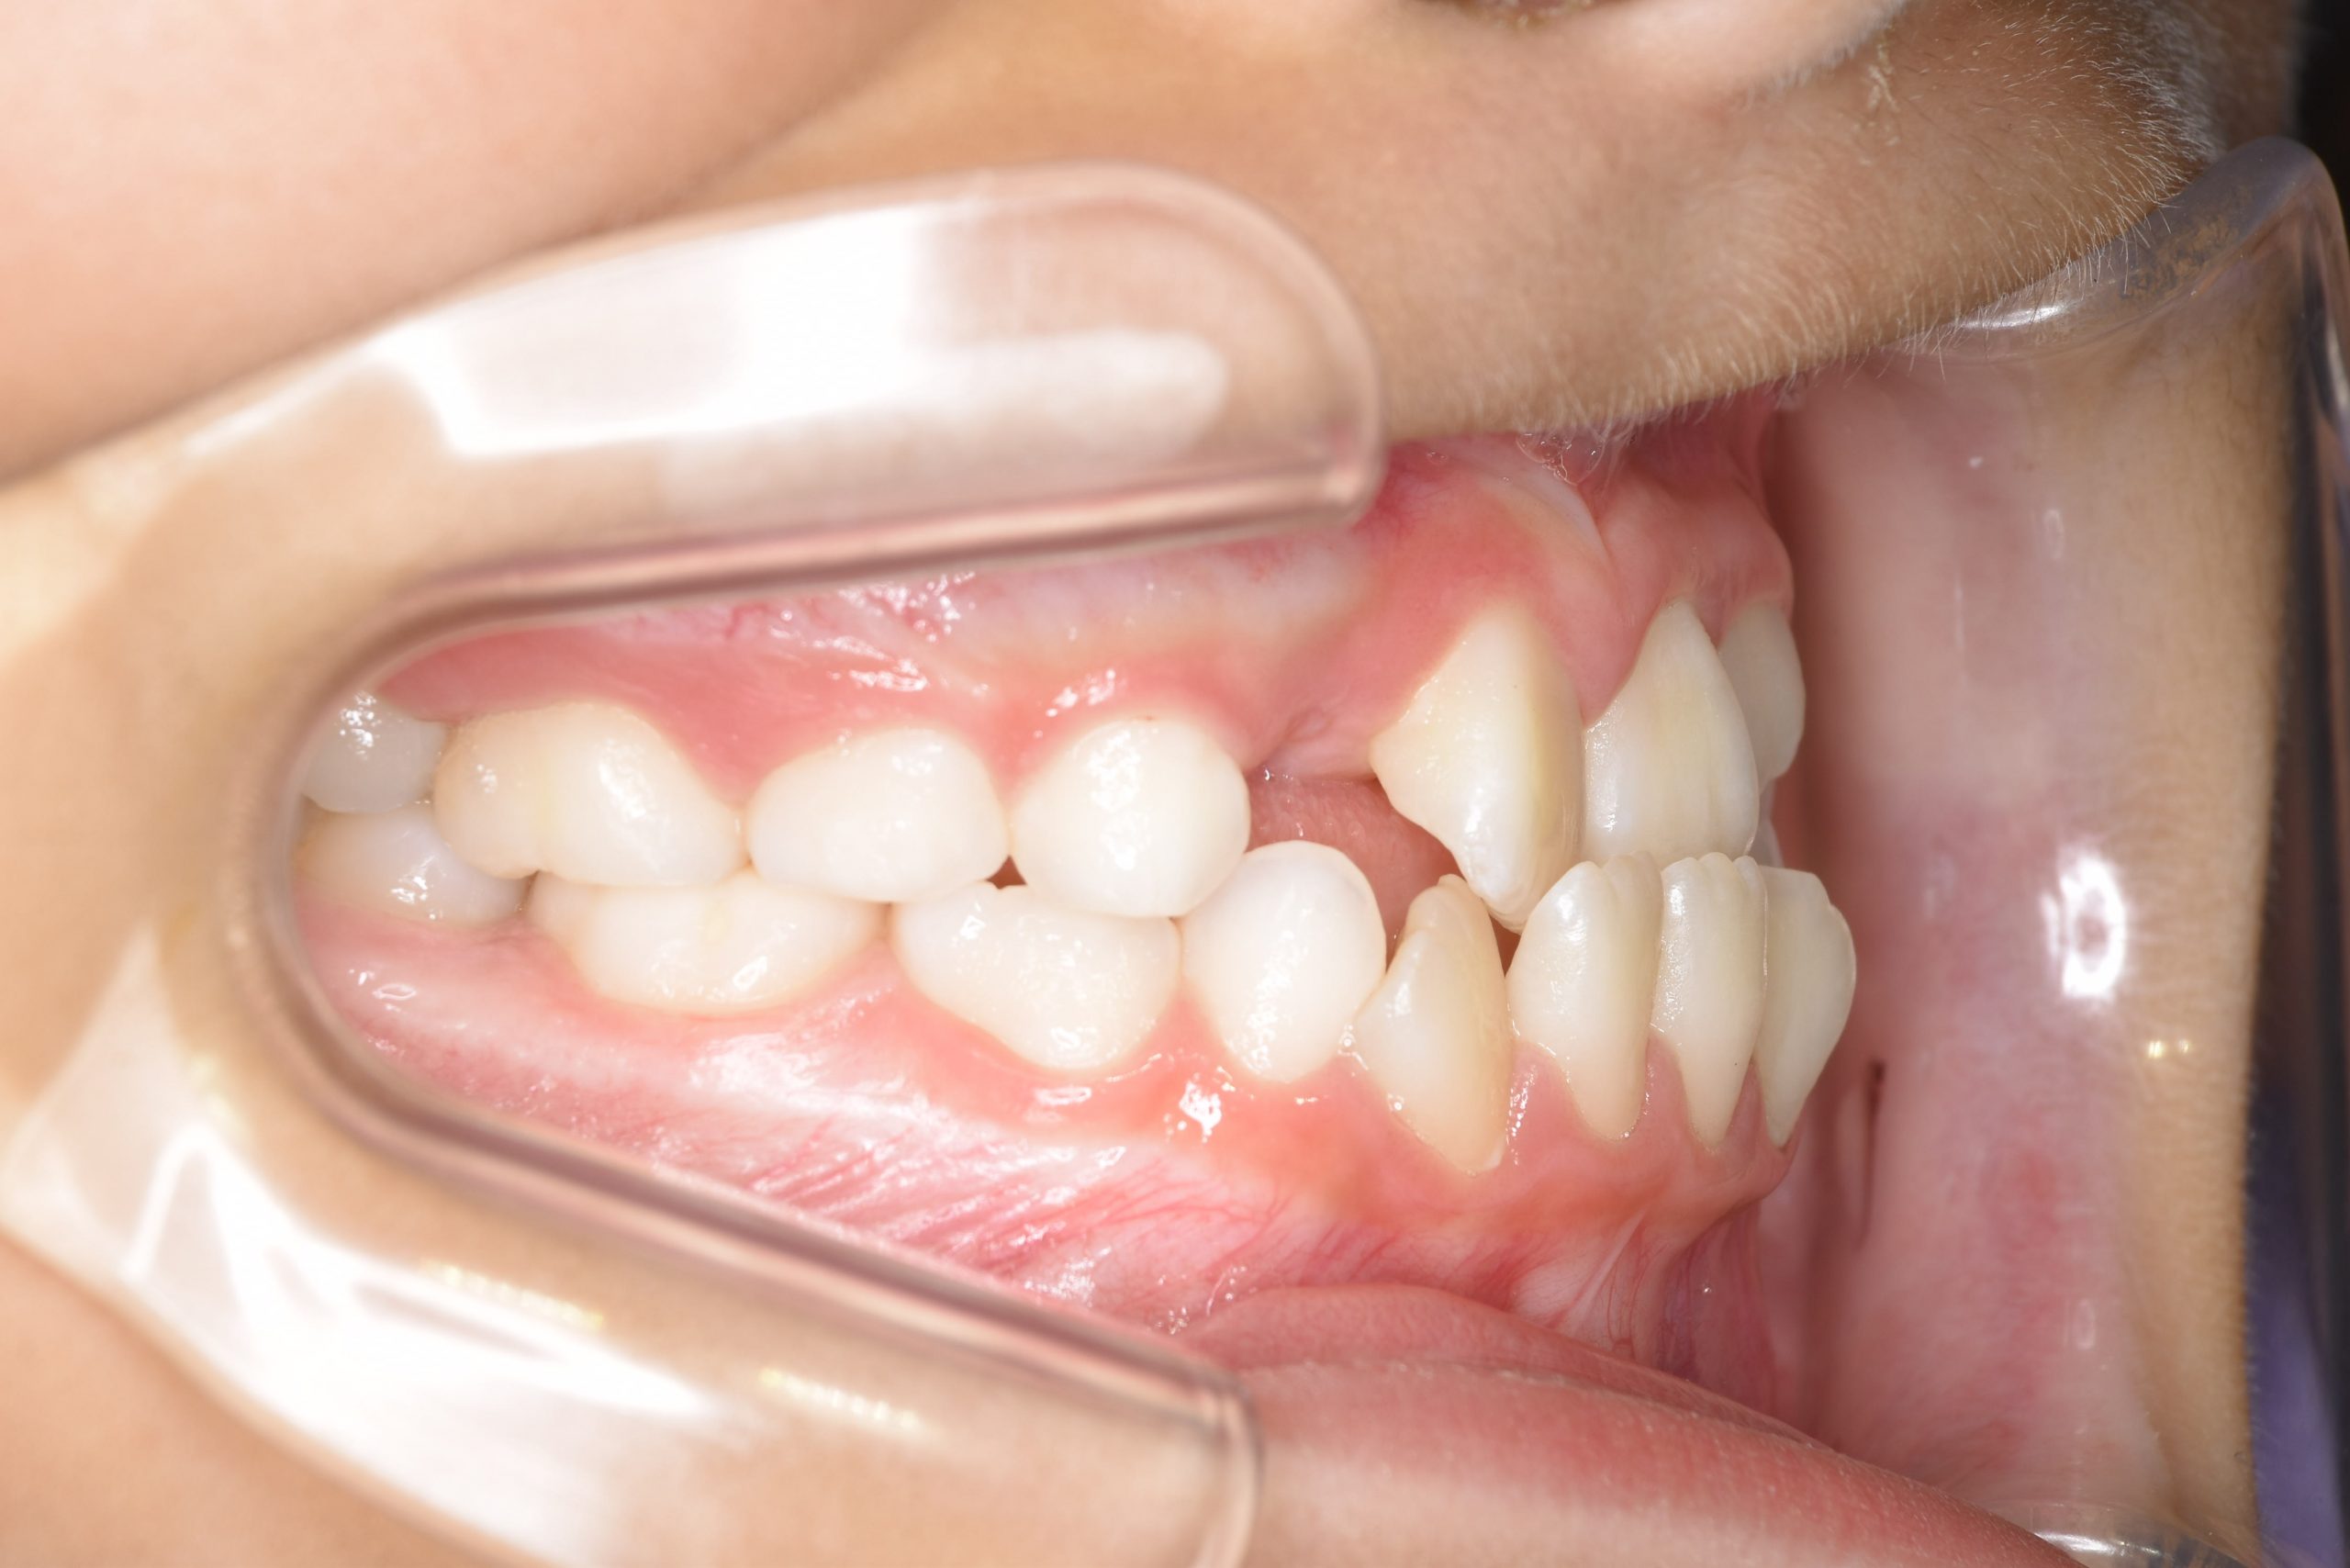

ビフォー

主訴 受け口

施術内容 上顎急速拡大装置と下顎リンガルアーチを用いて上下顎骨を拡大した。

上顎前方牽引装置を用いて上顎骨を前方に成長促進させた。

その後マウスピース型矯正装置で歯牙を配列し良好な咬合を獲得した。

治癒期間 2年9ヶ月間